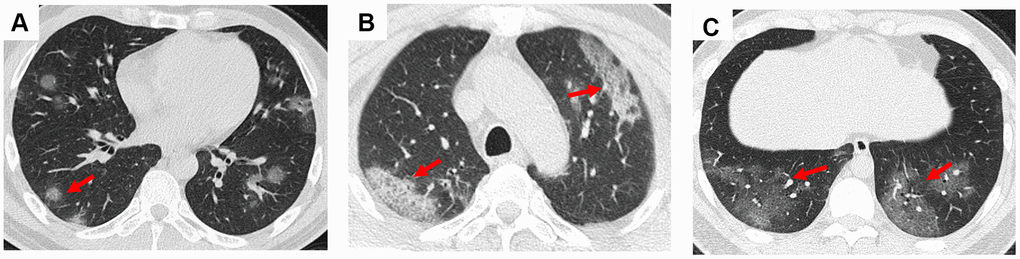

In this study, we presented some common and typical radiology changes (Figures 1 and 2). The most common radiology characteristic seen on the CT was ground-glass opacity (64/66, 97%). Most ground-glass opacities were characterized by scattered and bilateral lesions (Figure 1A and 1B). The CT scans of 15 (15/66, 23%) patients shown crazy paving (Figure 1C), and consolidation was observed in 7 (7/66, 11%) patients (Figure 2A). In addition, air bronchogram sign (47/66, 71%, Figure 1D), pleural traction (29/66, 44%), interlobular septal thickening (11/66, 17%), and halo sign (3/66, 5%, Figure 2B) were also observed (Table 2). Bronchiectasia was observed in the right lower lobe of one patient with bilateral ground-glass opacity (Figure 2C).

Figure 1. Ground-glass opacity and crazy paving in the CT scans of COVID-19 pneumonia patients. (A) Multiple nodular ground-glass opacity scattered in both lungs of a 44-year-old male patient; (B) Mixed ground-glass opacity along the long axis of subpleural in both lungs of a 67-year-old male patient; (C) Crazy paving was observed in the bilateral lower lungs of a 67-year-old male patient at the fourth day since admission. Typical lesions were marked with red arrows.